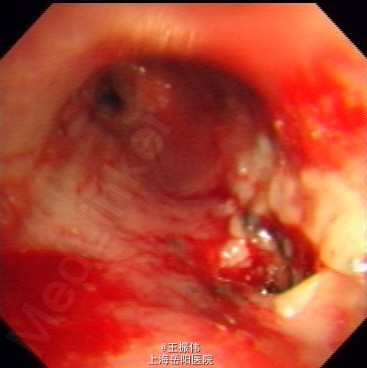

气管居中,颈静脉正常,胸廓两侧对称,无桶状胸,呼吸运动两侧对称,呼吸频率20次/分,肋间隙正常,无胸膜摩擦感。两肺叩诊清音,右肺可闻及湿性啰音,胸部CT:右肺上叶占位灶,两肺小结节灶,纵膈淋巴结增大,左肺下叶、右肺中叶炎症;两肺气肿伴肺大泡。组织病理【z155818】:灰白组织2粒,直径0.1cm。诊断:(左肺下叶开口)肉芽肿性炎,结核可能,请临床做相关病原体检测。支气管镜痰涂片:找到抗酸杆菌。